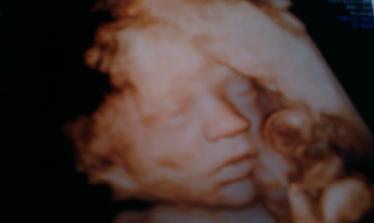

Liam-poslal nám ho anjel z neba

@xen21 veľmi kvalitné sono to bolo ale povedal aj pán doktor že je lepšie robiť takto fotočky lebo už je bábätko baculatejšie 🙂

Teším sa s tebou, že je Liamko úplne zdravučký.. zdravie je to najdôležitejšie, čo môže byť.. Liamko je kráááásny chlapček a ozaj podobnosť s Maxom je veľmi veľká, až neskutočné... úžasné... veľmi ti to prajem, budeš najlepšou maminkou pre svojho vytúženého drobčeka..šťastie sa začalo usmievať už aj na teba, čomu sa veľmi teším... zaslúžiš si to... tak želám pekný zvyšok tehotenstva a aj naďalej veľa veľa zdravíčka pre oboch..